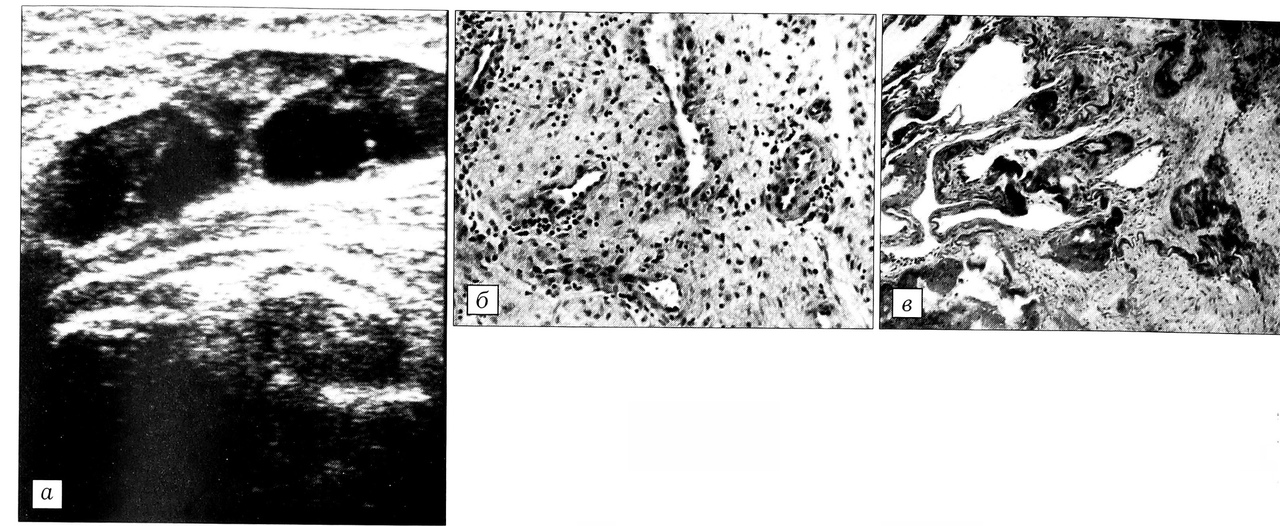

Рис. 3. Киста Бейкера, III период организации. а, б — сонограммы с продольным и поперечным сканированием: визуализируются изоэхогенное образование с четкими контурами и неоднородной внутренней структурой, ограниченные участки с незначительным внутренним эхо, резкое (до 16 мм) утолщение стенки кисты; в — гистологическая картина стенки кисты: отек и разволокнение соединительной ткани внутреннего слоя, воспалительно-пролиферативные изменения в глубоком слое (окраска гематоксилином и эозином, об. 63, ок. 10).

Третью группу составили 8 пациентов с III стадией гонартроза и давностью кисты 30±6 мес -(р < 0,05). При сонографии у них визуализировалось гипоэхогенное образование с четкими контурами и неоднородной внутренней структурой, с перетяжками и ограниченными участками без или с незначительным внутренним эхо. Стенка кисты была резко утолщена (более 8 мм), повышенной эхогенности. Нередко определялись эхоплотные, с акустической тенью включения. Шейка кисты дифференцировалась плохо (рис. 3, а, б).

На гистологических препаратах (рис. 3, в) внутренний слой стенки кисты в результате перестройки был представлен волокнистой соединительной тканью, в которой часто выявлялись дистрофические изменения в виде разволокнения и метахромазии. В глубоком слое сохранялись пролиферативно-воспалительные изменения, толщина его увеличивалась. В отдельных случаях происходило жировое перерождение соединительной ткани. Определявшиеся в просвете кисты соединительнотканные спайки становились более плотными и широкими. У 2 пациентов в стенке кисты были обнаружены небольшие участки некротизированного хряща, подвергающегося обызвествлению.

Сонографические и морфологические изменения структуры при большой давности кисты указывают на окончательную ее организацию, выражающуюся в резком утолщении стенки, наличии перетяжек и незначительном «жидкостном» содержимом с появлением в ряде случаев эхоплотных, с акустической тенью включений. Утолщенный внутренний слой приобретает строение плотной волокнистой ткани, подвергающейся дистрофическим изменениям. Спайки становятся более плотными и широкими. В утолщенном глубоком слое сохраняются пролиферативно-воспалительные изменения, в некоторых случаях происходит жировое перерождение соединительной ткани.

Такое состояние, характеризующееся дегенеративными изменениями тканей кисты Бейкера, относится к периоду окончательного формирования ее структуры с необратимостью патологического процесса.